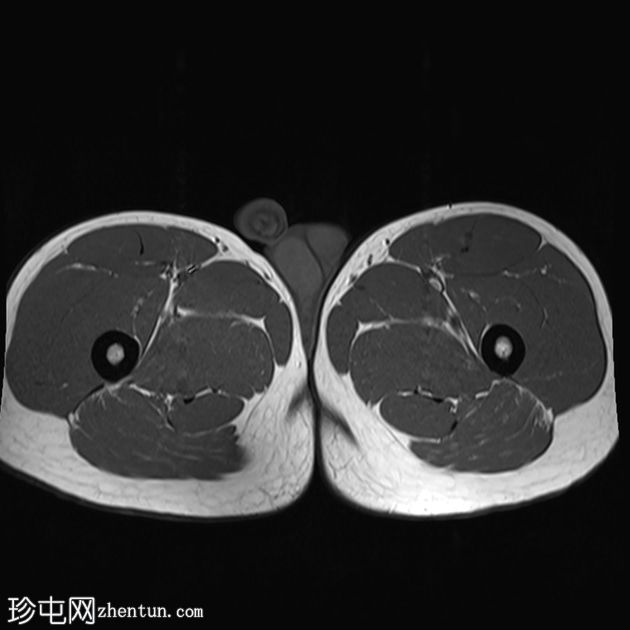

轴位

T1加权像

左侧股直肌近端肌腱交界处可见异常高信号,向远端延伸约至肌长一半。

可见清晰的充满液体的分离平面,呈“靶心征”,将双羽状间接头与浅表单羽状直接头分隔开,呈现出股直肌脱套样损伤的特征性影像

间接头肌纤维与近端肌腱保持连续,未见肌腱断裂或明显回缩。

可见轻度肌间及筋膜周围水肿。病例讨论